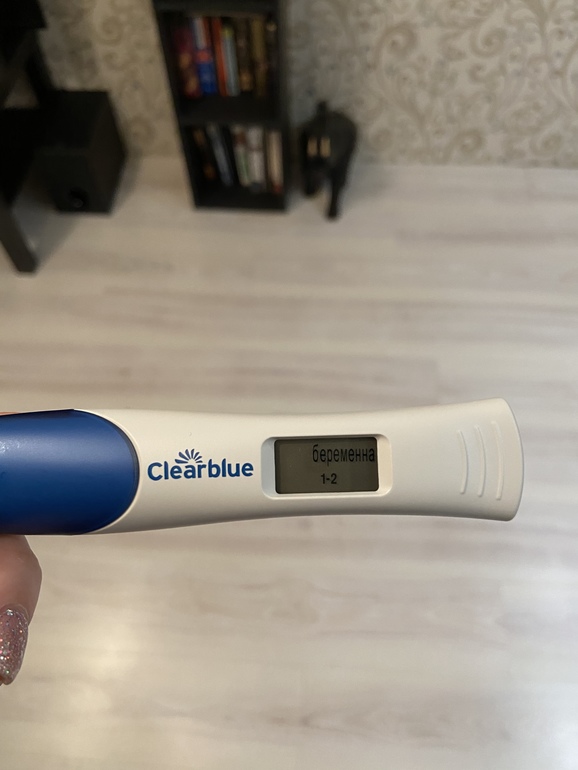

Прошу откликнуться, кто сталкивался. Ночью схватила резкая боль, после ПА. Утром помчала на УЗИ, где ставят диагноз: ЭХО признаки Диффузной формы аденомиоза. Кисты фолликулярной и КЖТ правого яичника. Апоплексии правого яичника.

Через 5ч только приём у Г....